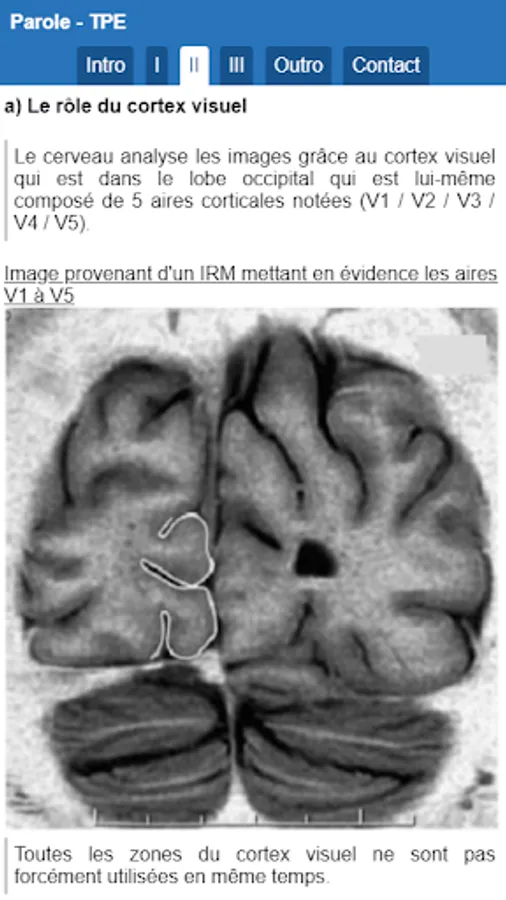

In this application you will learn how the brain is able to learn from the vision. You will discover how the eye, then you will discover how the image processing by the brain as well as the use of these images as part of an apprenticeship.